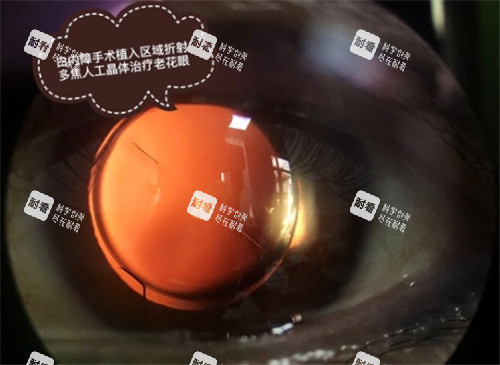

“免費手術(shù)用的晶體是不是質(zhì)量差?”這是許多患者的顧慮。實際上,國產(chǎn)折疊晶體已通過各國藥監(jiān)局認證,技術(shù)成熟,術(shù)后結(jié)果與進口晶體差異不大。例如,某國產(chǎn)單焦點晶體市場價約2000元,已廣泛應用于免費手術(shù),患者術(shù)后視力修養(yǎng)良好。若追求更高品質(zhì),可自費升級至多焦點晶體(市場價1.2萬-3萬元),但需評估自身經(jīng)濟能力。